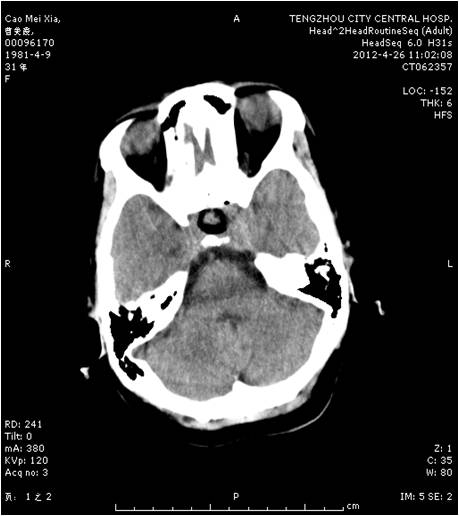

垂体瘤术前 垂体瘤术后